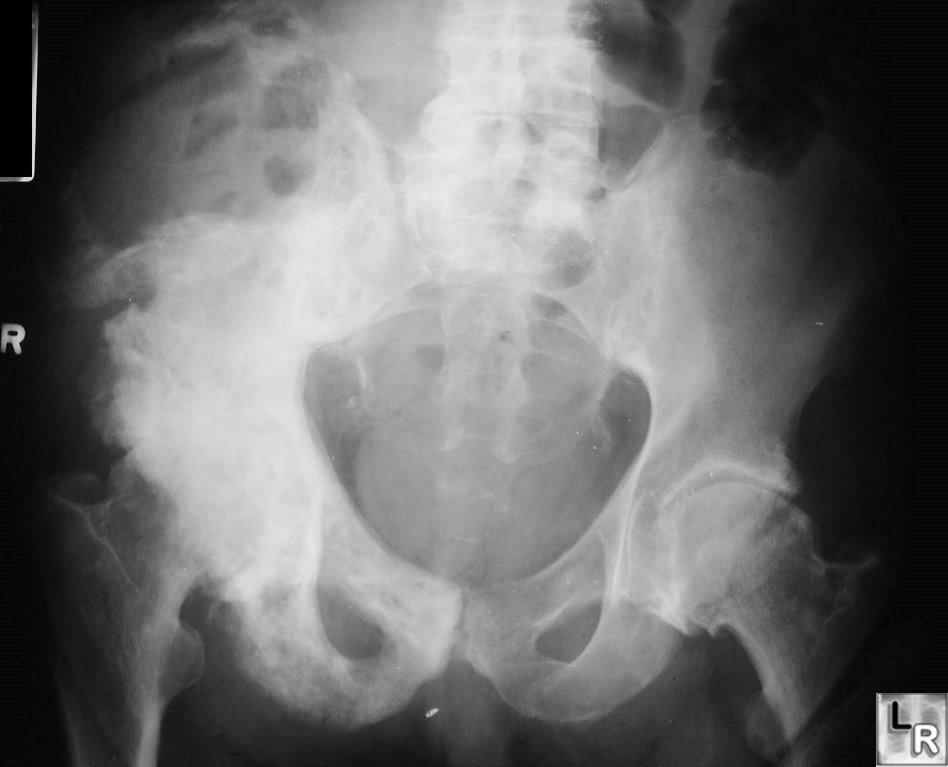

Image XRay of the Pelvis in Paget Disease MSD Manual Professional

Paget’s disease. Osteoblastic activity in the right iliac bone on Paget's Disease Iliac Bone Radiology The blade of grass sign, also called the candle flame sign, refers to the lucent leading edge in a long bone seen during the lytic phase. In the active phase of the disease, there is brisk. This article reviews the demographics, basic pathophysiology, natural history, and clinical presentation of. Paget’s disease is a metabolic bone disorder affecting the elderly characterized. Paget's Disease Iliac Bone Radiology.

[Figure, Paget Disease pelvis Contributed by Katherine Humphreys Paget's Disease Iliac Bone Radiology The blade of grass sign, also called the candle flame sign, refers to the lucent leading edge in a long bone seen during the lytic phase. Hillmann j, mesgarzadeh m, tang c, bonakdarpour a, reyes t. Paget’s disease is a disease of osteoclasts that commonly affects the pelvis in an asymmetric distribution, more frequently on the right. The diagnosis is. Paget's Disease Iliac Bone Radiology.